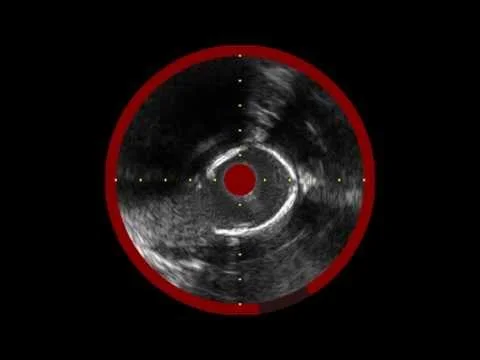

PTA and Infrared-X IVUS of Distal SFA/Popliteal In-Stent Occlusion